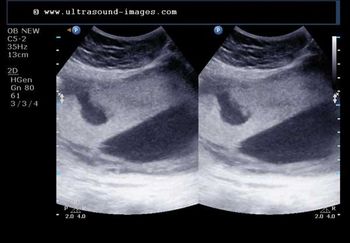

This 53 year-old woman has a uterine lesion and irregular bleeding. Which of the following is the correct diagnosis?